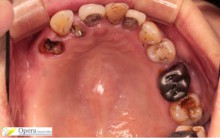

治療後

入れ歯のばねがかかるところにかぶせ物をしています。

入れ歯のばねがかかりやすいように、本来の歯の形と若干形を変えています。